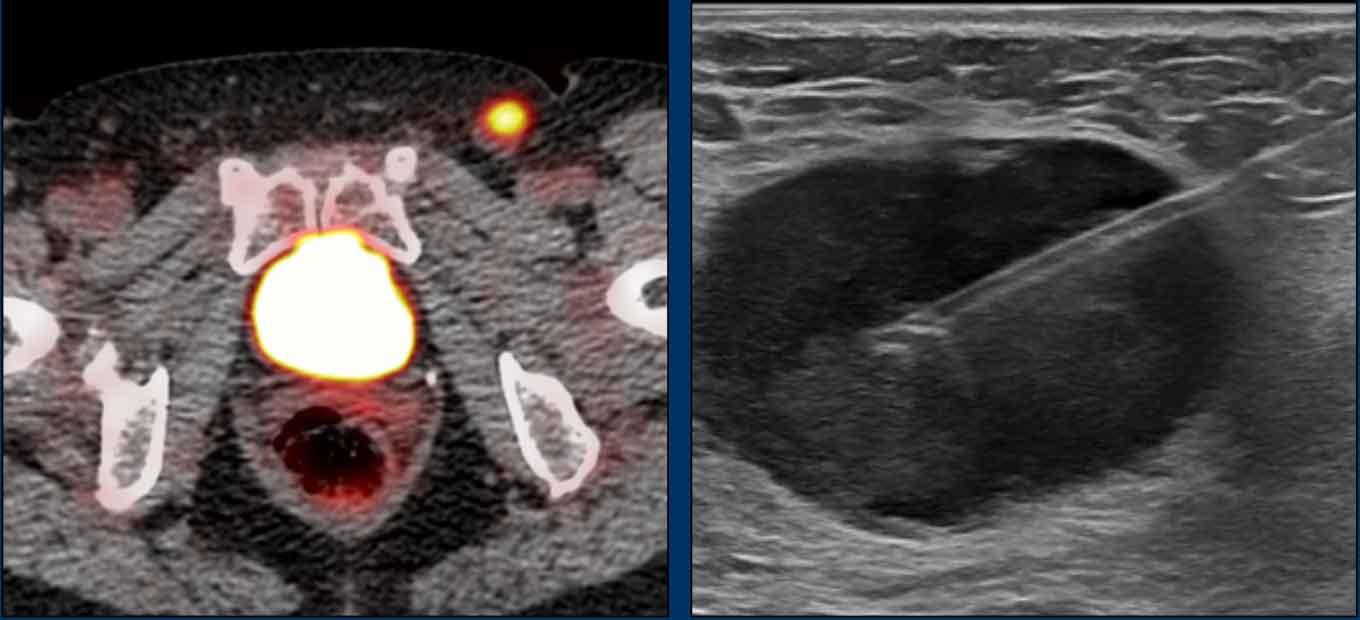

Các hình ảnh này của một bệnh nhân ung thư hậu môn.

Hình ảnh

MRI cho thấy một hạch bạch huyết to rõ rệt (đường kính trục ngắn 1,5 cm) liền kề mạch chậu trong, được phân giai đoạn là N+ trên MRI.

FDG-PET CT cho thấy tăng hấp thu FDG bệnh lý tại hạch, xác nhận đây là hạch N+.

Trong trường hợp này có hai hạch bạch huyết nhỏ trong mạc treo trực tràng được đánh giá là không rõ ràng trên MRI.

FDG-PET cho thấy tăng hấp thu FDG rõ rệt tại các hạch nhỏ này, thể hiện lợi ích bổ sung của PET so với MRI trong phân giai đoạn hạch ung thư hậu môn.

Bệnh nhân cuối cùng được phân giai đoạn là T2 N1a.